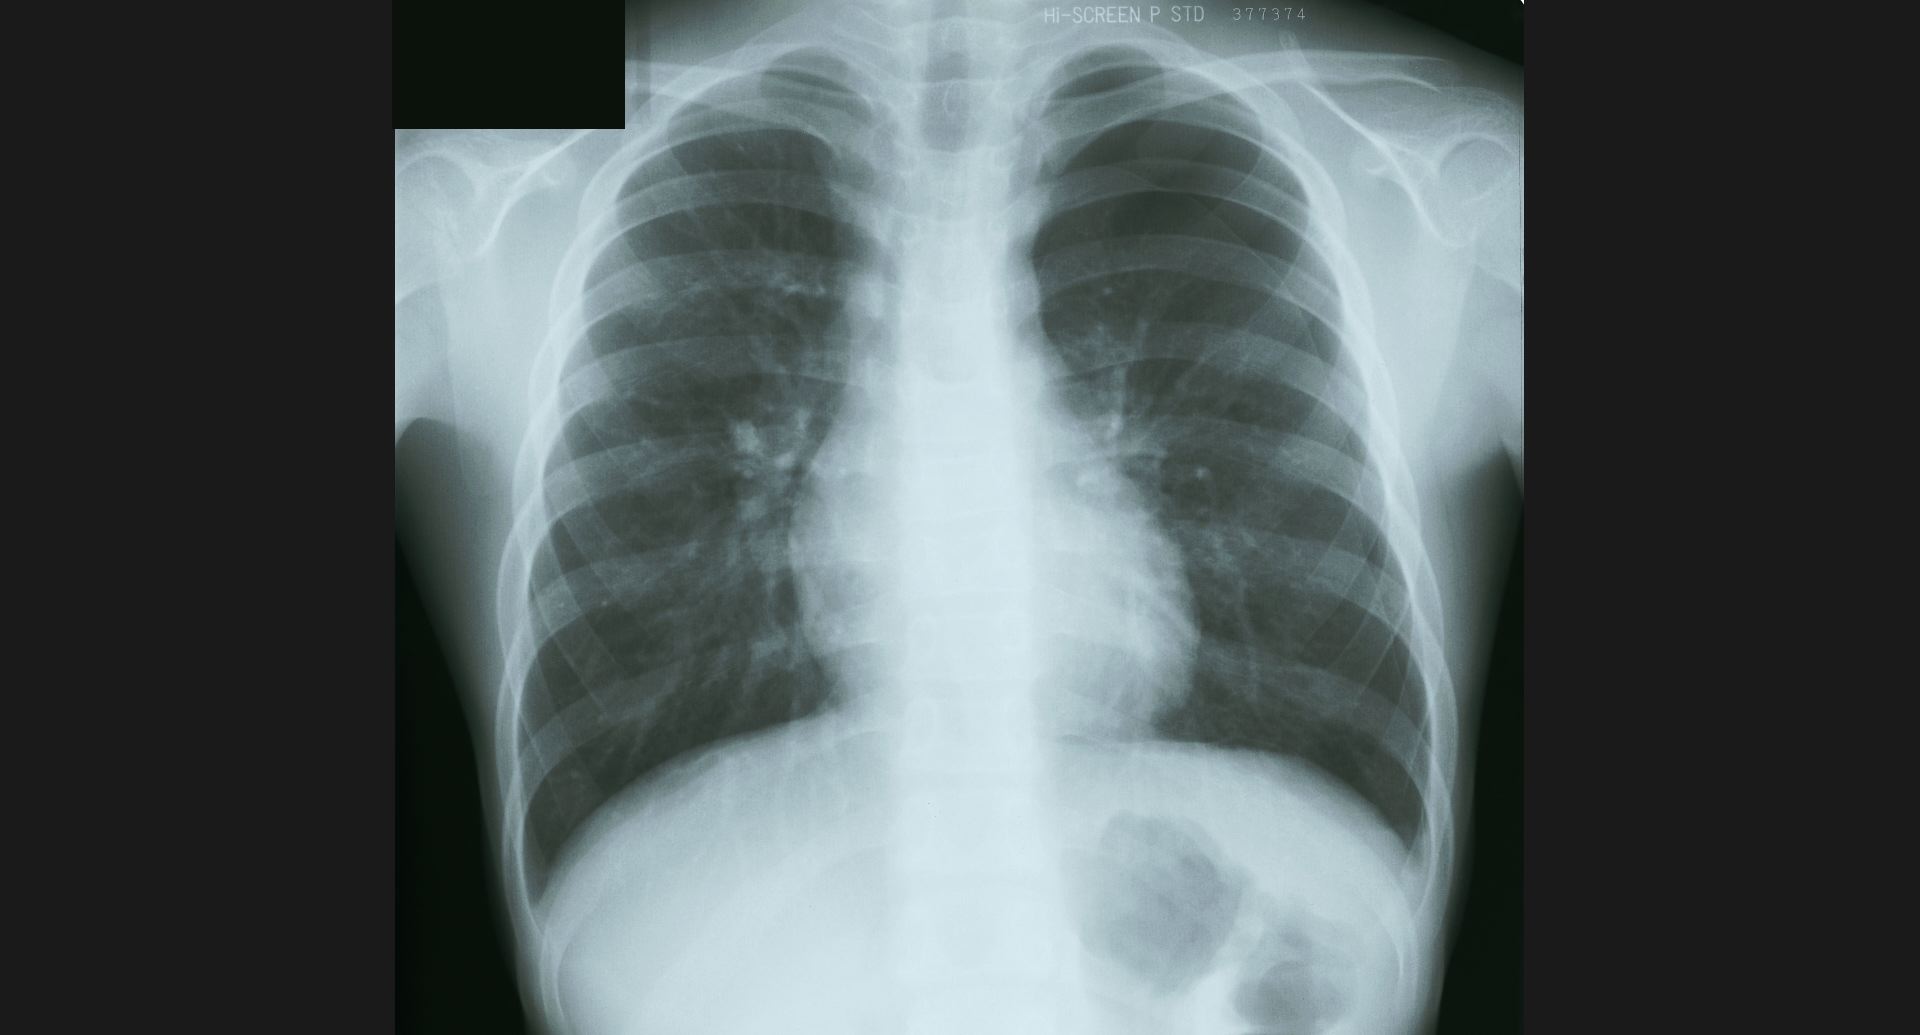

fig.1(117KB) :Alveolar microlithiasis

細かい肺病変、air bronchogram。